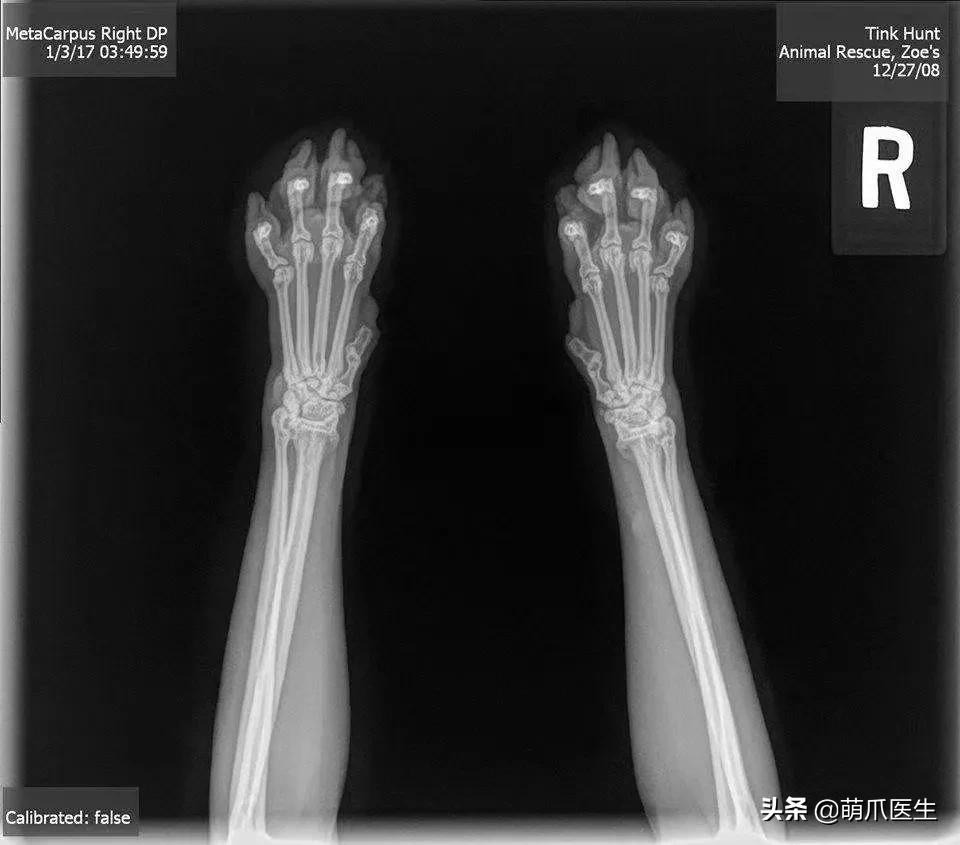

但可以明确的是,猫咪骨骼发育完全时,爪爪的X光片绝对就长这样:

或许,真的是岁月夺走了猫爪卖萌的权力吧……